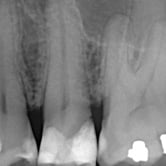

Granuloma Periapical

Un granuloma periapical es una pequeña masa de tejido inflamatorio en la punta de la raíz del diente, generalmente como respuesta a una infección crónica.

Los pacientes pueden no sentir dolor, pero el área puede estar sensible al tacto.

El tratamiento de conducto es necesario para eliminar la fuente de la infección y permitir la curación del tejido.

Quiste Periapical

Un quiste periapical es una cavidad llena de líquido en la punta de la raíz del diente, generalmente resultado de una infección crónica.

Los pacientes pueden notar una hinchazón sin dolor en la encía.

El tratamiento incluye el tratamiento de conducto y, a veces, la extirpación quirúrgica del quiste. Si no se trata, el quiste puede crecer y causar complicaciones.